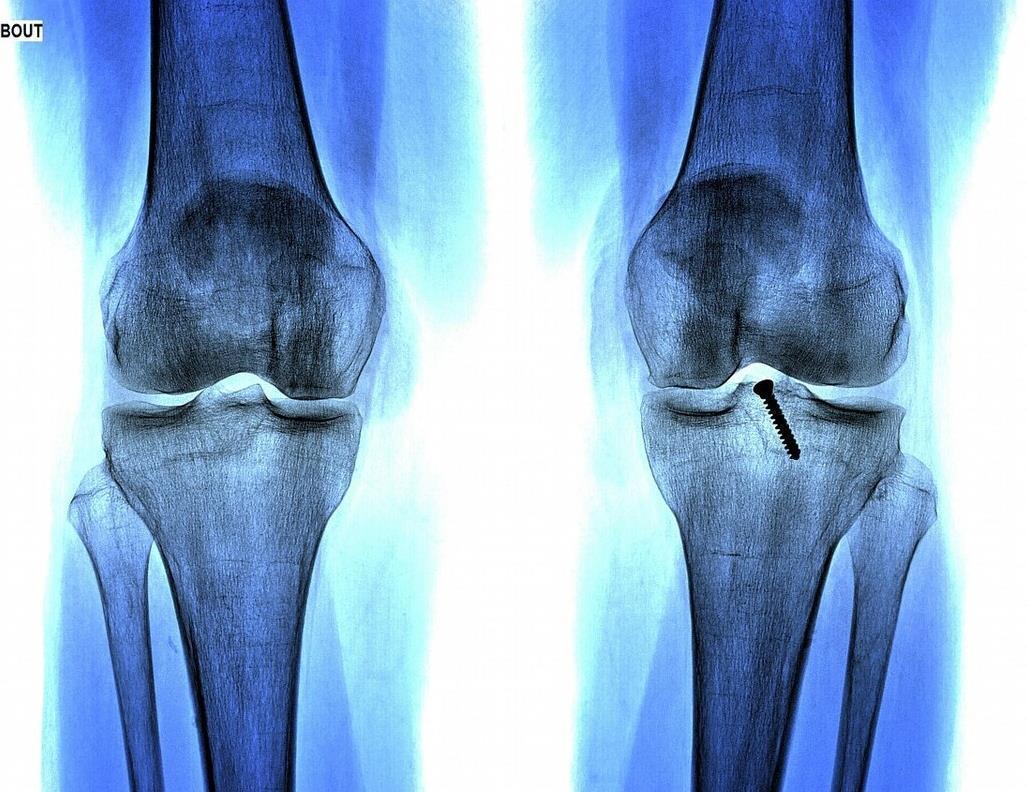

听到别人夸自己的儿子,庆庆父母当然开心了,也没有觉得孩子的身体会有什么问题,直到学校里组织体检,医生告知庆庆父母:孩子的骨骺线已经完全闭合了,再也不会长高了!庆庆父母心里打鼓,但是不相信,就带着孩子去大医院做了个全面检查,结果却是一样的,这让庆庆父母直接崩溃了。

检查结果出来后,根据和医生的一番交谈才知道,最终害孩子长不高的“元凶”是自己,是自己给庆庆吃的营养太丰盛,高估了孩子脾胃运化能力,提前透支了孩子的发育潜能,致使孩子骨骺线闭合,导致孩子过早停止发育。因此,给孩子好吃好喝的,并不是好事,相反,有时候可能是害了孩子。